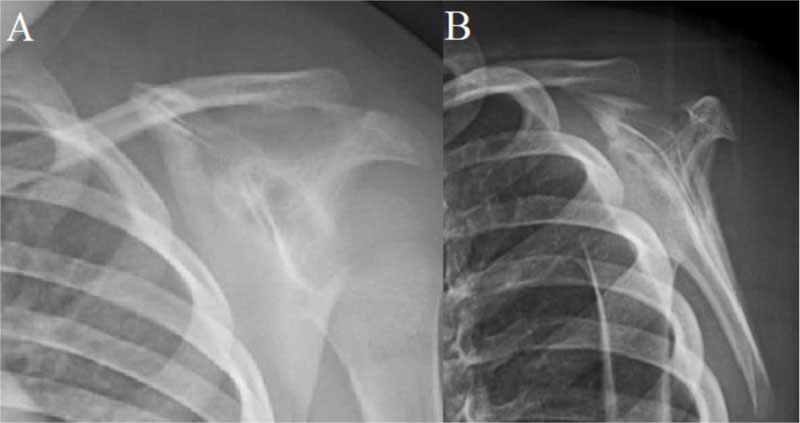

Fig. (1)

Initial radiographs. A radiolucent lesion with motheaten borders is seen on AP (

A

) and scapular spine (

B

) views.